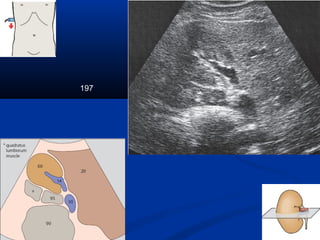

197

Kyõ thuaät : caùc maët caétKyõ thuaät : caùc maët caét